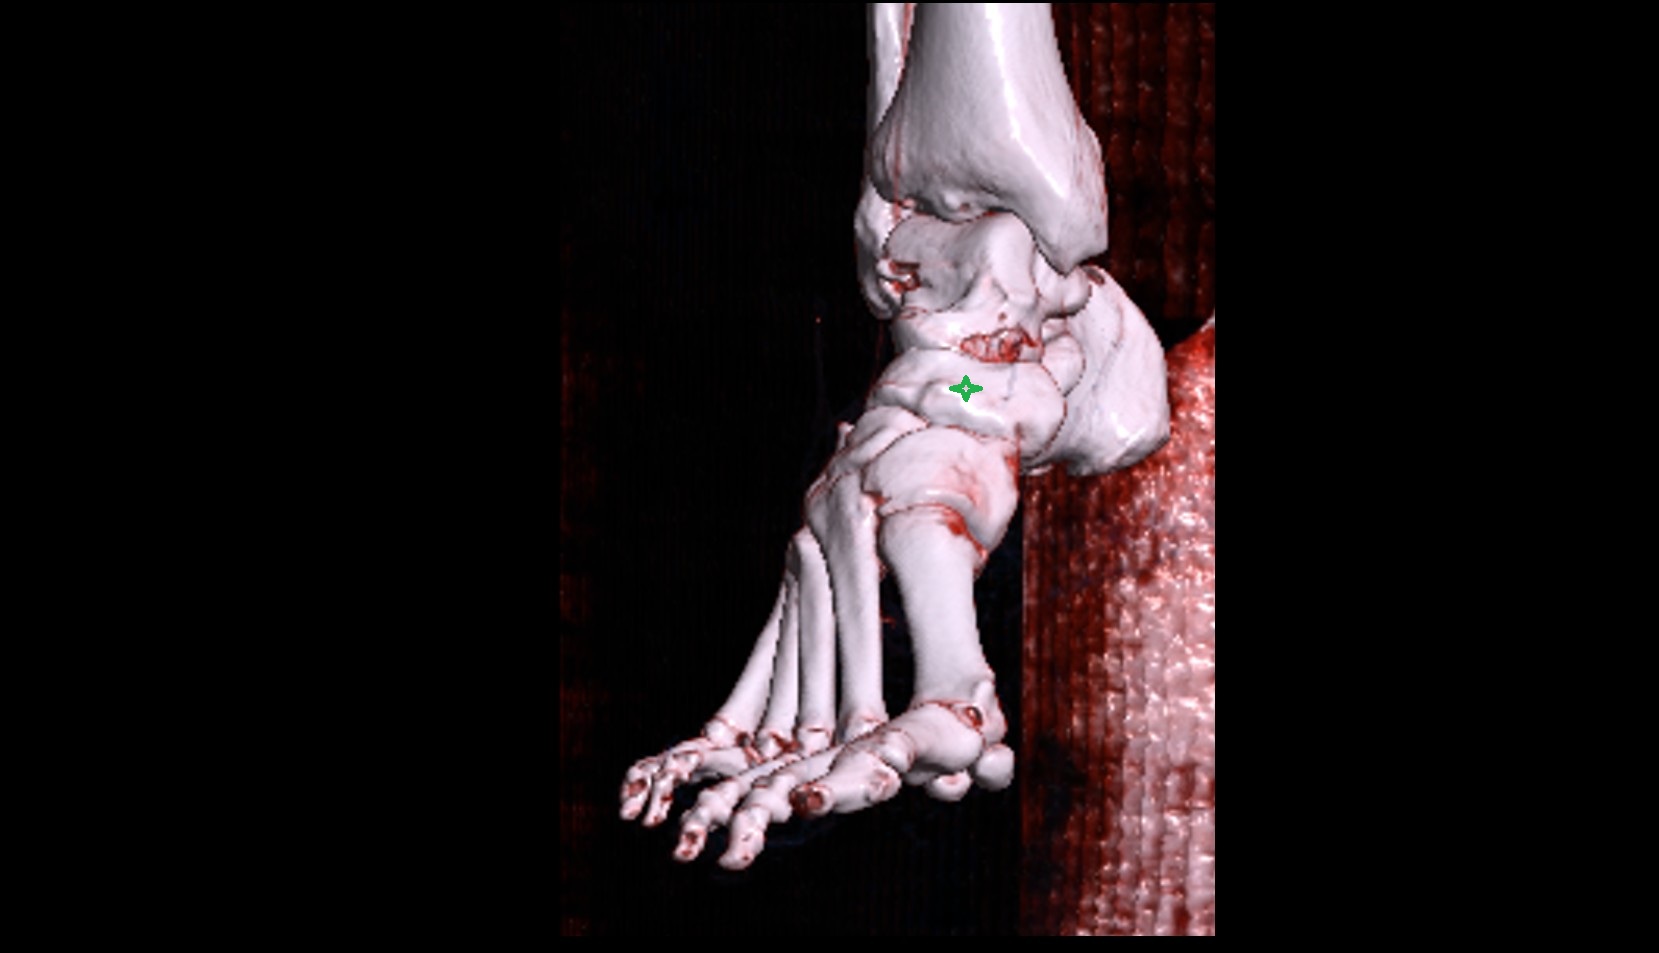

- Talus

- Head of talus

- Body of talus

- Neck of talus

- Calcaneus

- Anterior process of calcaneus

- Sustentaculum tali

- Cuboid

- Ankle joint

- Talocalcaneal joint

- Talocalcaneonavicular joint

- Calcaneocuboid joint